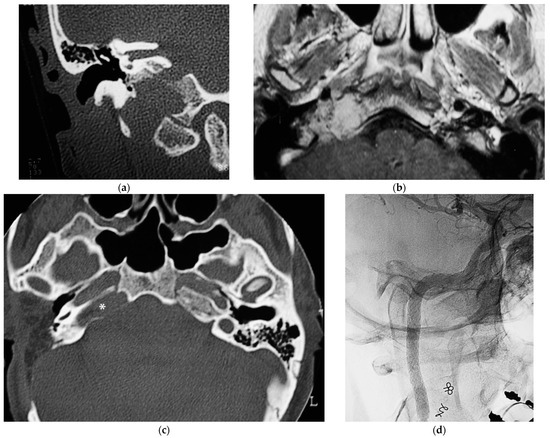

5.1. Case 1: (C4Di2)

5.2. Case 2: (C3Di1 + Stage I VP)

5.3. Case 3: (C4Di2Vi)

5.4. Case 4: (C3Di2 + Stage II Vagal PGL)

5.5. Case 5: (C3Di2Vi)

5.6. Case 6: (C4Di2Vi)